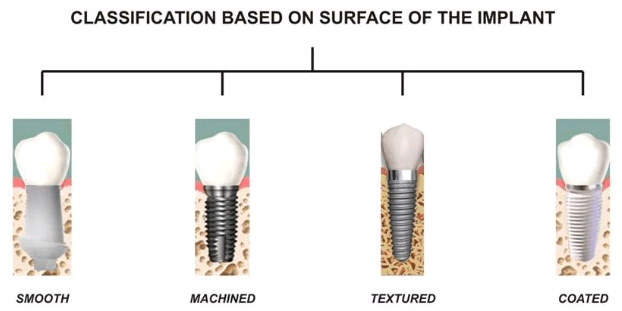

What are the 4 types of implants?

Four Types of Tooth Decay This may interest you : What is the average cost of dental implants.

- Two-Step Dental Forum:

- Last / Last Toothache:

- Professional Psychologists:

- Subperiosteal Dental Implants: